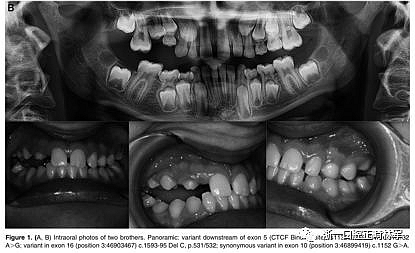

兄弟姐妹被診斷為I型PFE并顯示雙邊呈現(xiàn)。該變體(PTH1R基因的外顯子5的下游c.313×32 A.G)發(fā)生在與轉(zhuǎn)錄因子相互作用的調(diào)節(jié)區(qū)中。除了這種突變之外,這些兄弟還受到第二個(gè)突變的影響,這些突變對(duì)每一個(gè)都是獨(dú)特的:一個(gè)兄弟姐妹(II:1)也存在在外顯子16的基因氨基末端發(fā)生的移碼缺失,c.1593DelC ,第(Pro532Leufs *)(圖1A,B)。在另一個(gè)同胞(II:3)中,鑒定出在蛋白質(zhì)氨基酸序列水平不引起變異的外顯子,c.1152GA(rs200475872;圖1A,B)中的同義變體,但涉及改變含氮堿?;谟?jì)算機(jī)分析,這種改變可能會(huì)影響mRNA的折疊并影響其半衰期和蛋白質(zhì)生產(chǎn)。在這個(gè)患者樣本中,在一個(gè)孤立的病例中發(fā)現(xiàn)了同樣的同義變體c.1152G.A,由于PFE而具有嚴(yán)重的開合(圖2)。

圖2.口內(nèi)照片。全景:外顯子10中的同義變體(位置3:46899419)c.1152 G>A.

本研究中確定的低咬合的臨床特征與PFE基于基因診斷和萌出障礙診斷標(biāo)準(zhǔn)的應(yīng)用相一致。對(duì)特定相關(guān)牙科特征的仔細(xì)臨床檢查包括以下內(nèi)容:至少一顆牙包括低咬合,局限于后部區(qū)域,單側(cè)(38%;圖1A)和雙側(cè)呈現(xiàn)(35%;圖1B和2),至少有一個(gè)暫時(shí)性后牙(48%暫時(shí);圖1A,B和3A; 55%永久性,圖3B)。此外,觀察到牙面特征如下:由于受影響側(cè)的側(cè)向開放咬傷的嚴(yán)重程度而引起的垂直骨骼不對(duì)稱(35%;圖1A,B和圖3A,B);由下頜骨側(cè)向偏離組成的面部不對(duì)稱(圖1A,B和圖2;表4)。這種不對(duì)稱在單側(cè)開合患者中更為明顯。進(jìn)一步發(fā)現(xiàn)受影響的患者與先前報(bào)道的患者存在上頜骨收縮和III類牙齒/骨骼關(guān)系(28%;圖1A,B和圖2)。至少有一例患者出現(xiàn)了相對(duì)于9名患者的低咬合。表4總結(jié)了PTH1R的表型結(jié)果和相關(guān)的突變分析(N = 8)。